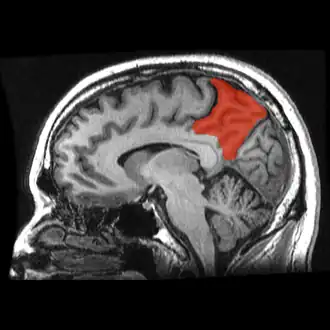

![]() Medial surface of left cerebral hemisphere. (Precuneus visible at top left.) (Anterior to the right.) | |

![]() Sagittal MRI slice with the precuneus shown in red. (Anterior to the left.) | |